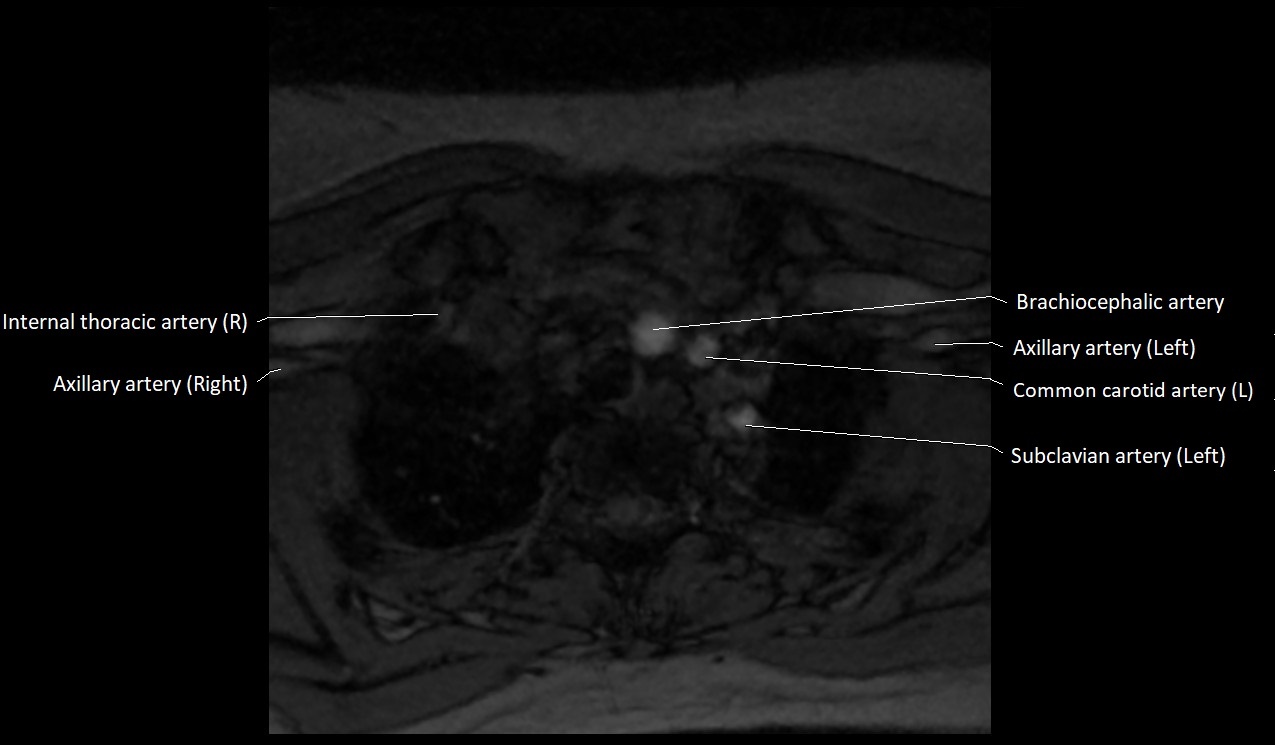

MRI images

image